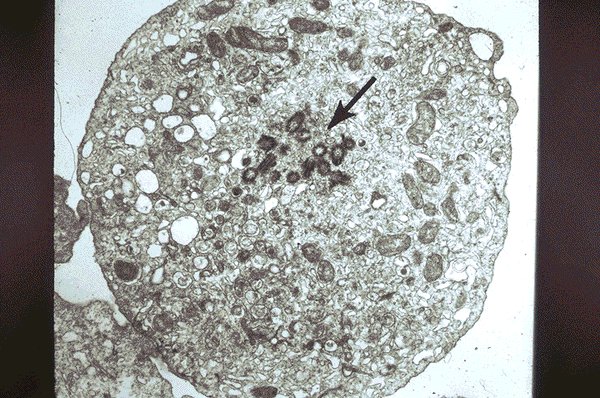

ANLL-M-7 electron micrograph of an M-7

megakaryoblast

This electron photomicrograph shows a

megakaryoblast in a patient with acute non-

lymphoblastic leukemia, FAB type M-7. Small

specific granules are seen, which identify this cell

as being of the megakaryocytic line.